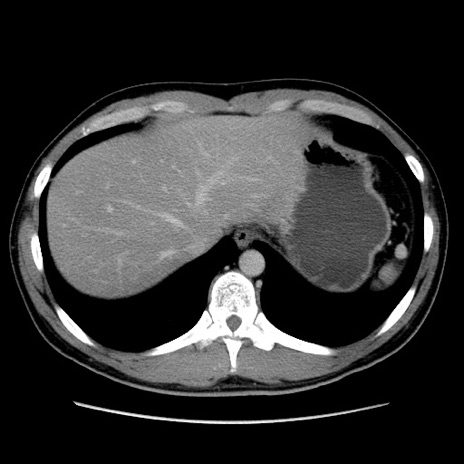

症例36(横断像)

【症例】20歳代 男性

【主訴】心窩部痛

【現病歴】今朝より上腹部痛あり。一旦軽快していたが再度出現したため救急要請。昨日夕に白身の魚を含む刺身を食べた。

【身体所見】BP 136/89mmHg、HR 74/min、BT 37.0℃、腹部:膨満、軟、心窩部に圧痛あり。反跳痛なし、筋性防御なし、腸雑音やや亢進あり。

【データ】WBC 17700、CRP 0.48